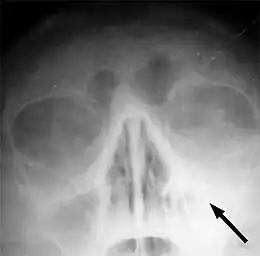

Le sinus maxillaire gauche marqué d'une flèche. On note l'absence de transparence aérique par rapport au côté opposé.

Une radiographie n'est utile qu'en cas de doute sur le diagnostic ou éventuellement après un premier échec de traitement par antibiotiques. Le scanner n'est quant à lui indiqué qu'en cas de suspicion de sinusite complexe ou sphénoïdale, cette dernière n'étant pas visible par radiographie.